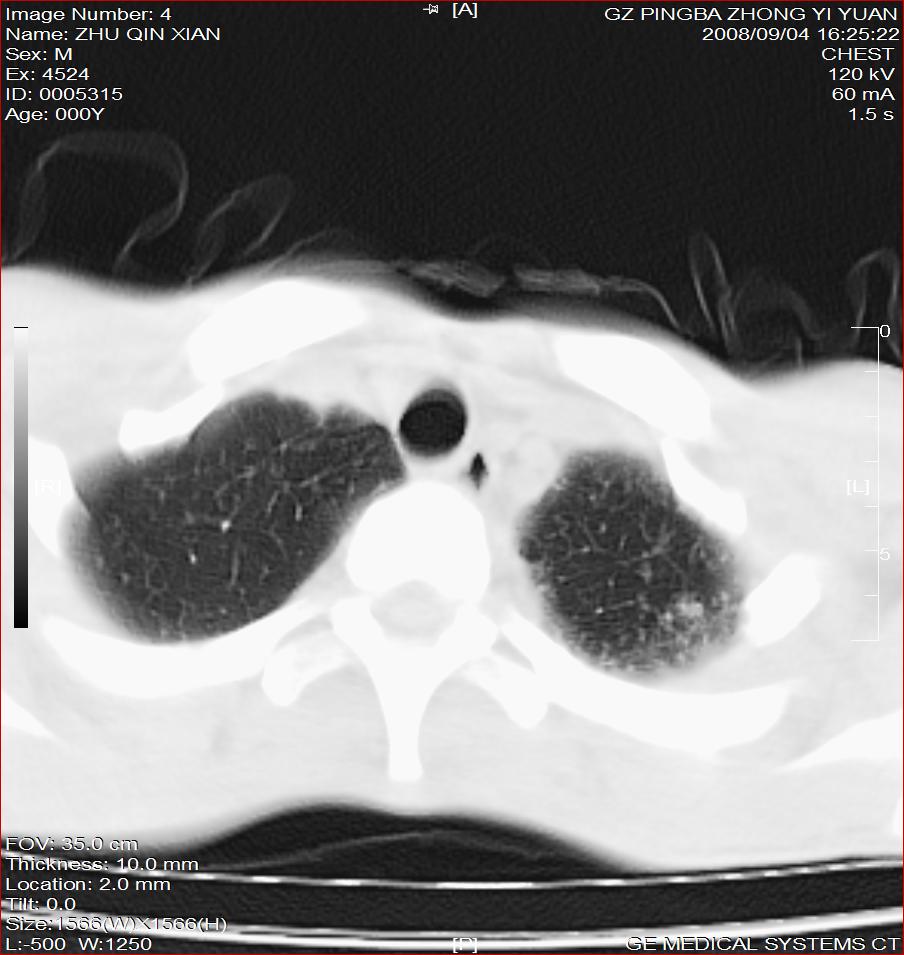

以下是引用随光逐影在2008-9-4 20:05:00的发言:[br]1)考虑两肺结核。2)左侧胸膜炎(胸膜肥厚、粘连,胸腔积液)。3)左侧局限性气胸。

以下是引用子十在2008-9-4 19:34:00的发言:[br]左上肺结核并空洞及双肺播散。节段性肺不张、胸腔积液、胸膜肥厚粘连。[br]